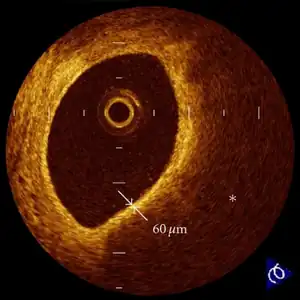

Thin-cap fibroatheroma (TCFA) often observed in the culprit lesions of acute coronary syndrome.[10]

In those who have ACS, atheroma rupture is most commonly found 60% when compared to atheroma erosion (30%), thus causes the formation of thrombus which block the coronary arteries. Plaque rupture is responsible for 60% in ST elevated myocardial infarction (STEMI) while plaque erosion is responsible for 30% of the STEMI and vice versa for Non ST elevated myocardial infarction (NSTEMI). In plaque rupture, the content of the plaque are lipid rich, collagen poor, with abundant inflammation which is macrophage predominant, and covered with a thin fibrous cap. Meanwhile, in plaque erosion, the plaque is rich with extracellular matrix, proteoglycan, glycoaminoglycan, but without fibrous caps, no inflammatory cells, and no large lipid core. After the coronary arteries are unblocked, there is a risk of reperfusion injury due spreading inflammatory mediators throughout the body. Investigations is still underway on the role of Cyclophilin D in reducing the reperfusion injury.[11]